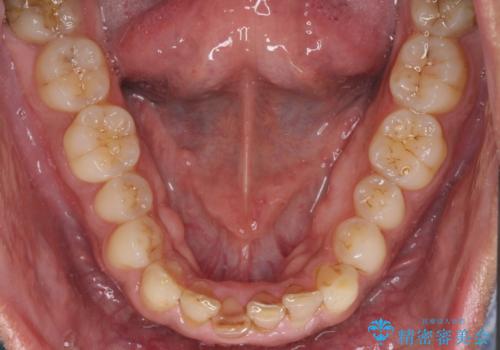

- 下の前歯がすり減って、痛みがあるとのことで来院された患者様です。

咬合力が強く、4本のうち3本の歯が失活しており、腫れや痛みが認められました。

3歯に根管治療を行い、その後4歯をオールセラミッククラウンにて補綴することとしました。

根管治療により腫れと痛みが引き、叢生の認められた歯列は補綴治療により改善され、清掃性が増しました。